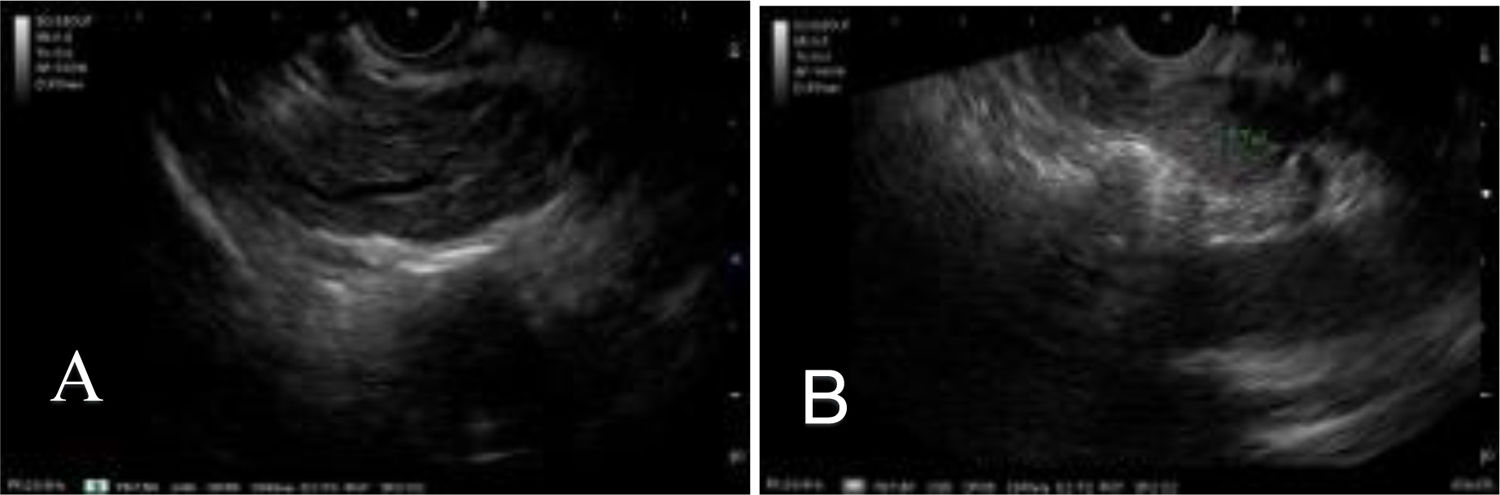

The USE was carried out under general anesthesia, with a linear echoendoscope, enabling detailed evaluation of the pancreatic parenchyma (diffuse enlargement), main pancreatic duct, and contiguous organs (Fig. 1). Using a 22 G Franseen fine-needle biopsy needle, samples were obtained from the head of the pancreas, via the transduodenal approach, and the body of the pancreas, via the transgastric approach, preventing vascular damage through the Doppler technique (Fig. 2). One needle pass was carried out in each region, using the fanning technique, with the slow removal of the stylet to maximize the sample yield (Fig. 2). No intraoperative or postoperative complications were registered.

(A) Body and (B) tail of the pancreas with minor Rosemont criteria for chronic pancreatitis9,10) (hyperechoic traces with no acoustic shadow and hyperechoic enhancement of the walls of the main pancreatic duct).